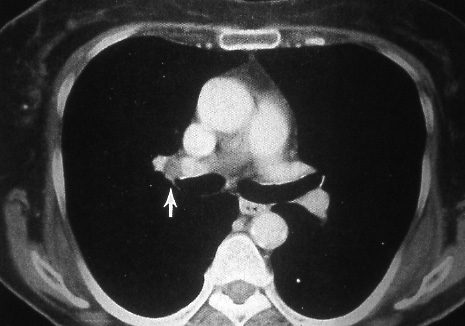

Fig. 38c: Computed tomographic scan (soft tissue windows) shows a right hilar node (arrow) that was proven to contain metastatic disease.